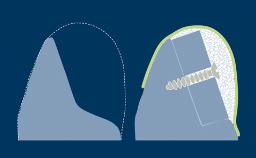

拔牙后,支撑牙齿的牙槽骨会随着时间的推移而发生吸收。这种吸收会导致牙槽骨量减少,如此右上中切牙缺失的临床示例所示。颊舌向骨宽度显著减小,这与将种植体植入以修复为导向确定的正确三维位置的口腔种植基本要求存在冲突。当牙槽骨发生吸收后,通常需要增加骨量以确保可以正确植入种植体且种植体完全嵌入骨中。本模块将介绍一种称为引导骨再生 (GBR) 的特定骨增量技术。

- 描述引导骨再生 (GBR) 的生物学原理